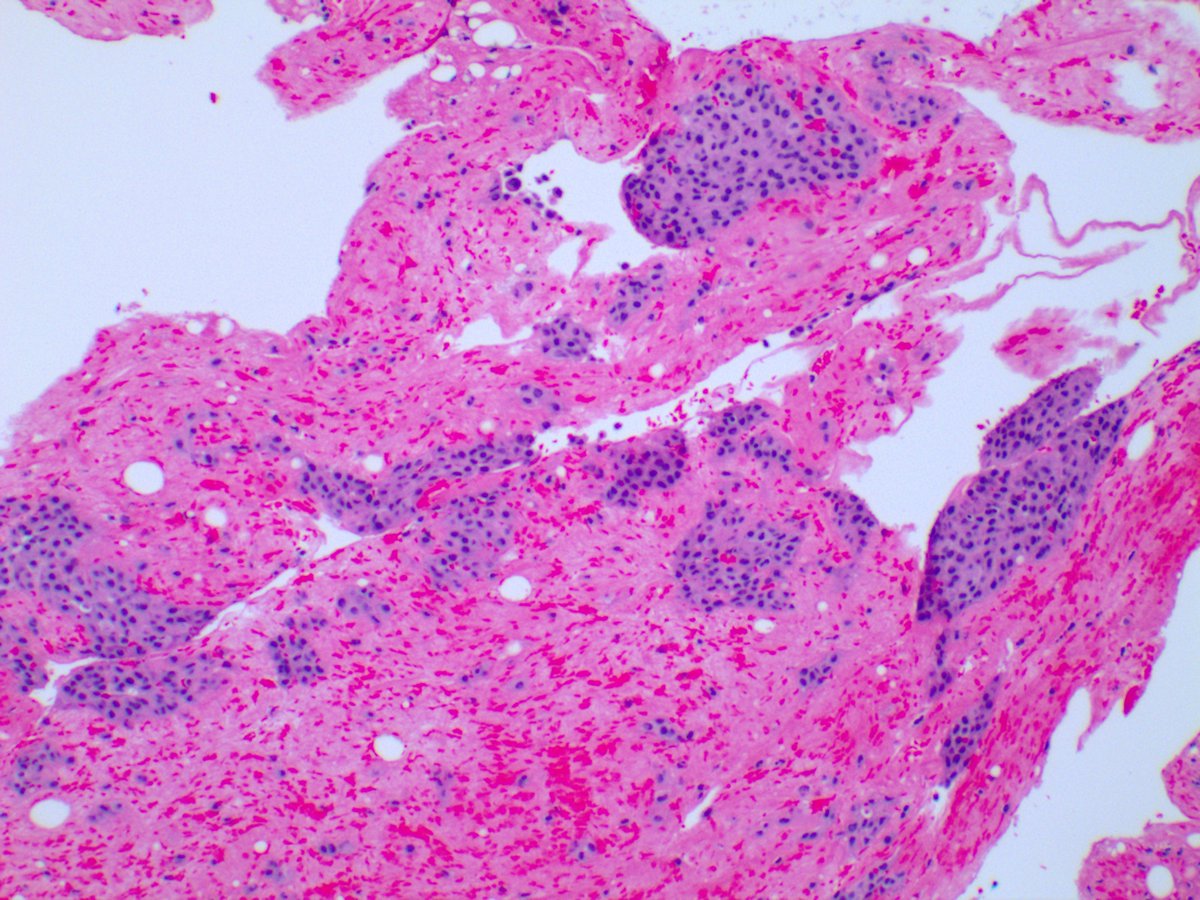

4. Getting back on track, our little lady in question two was married to this 74-year-old male, who also dabbled with asbestos sculptures in his garage. He too presents with a pleural rind.

This time, we have two components - epithelioid and sarcomatous. Typically, CK5/6 should not stain the sarcomatous portion of the tumor [not done, unfortunately]. WT1 and Calretinin are shown here.

If present, which of the following mutation are specific for mesothelioma?

BAP1 and MTAP, if present, are 100% specific for mesothelioma. Another good one to remember is homozygous deletion of CDKN2A (p16).